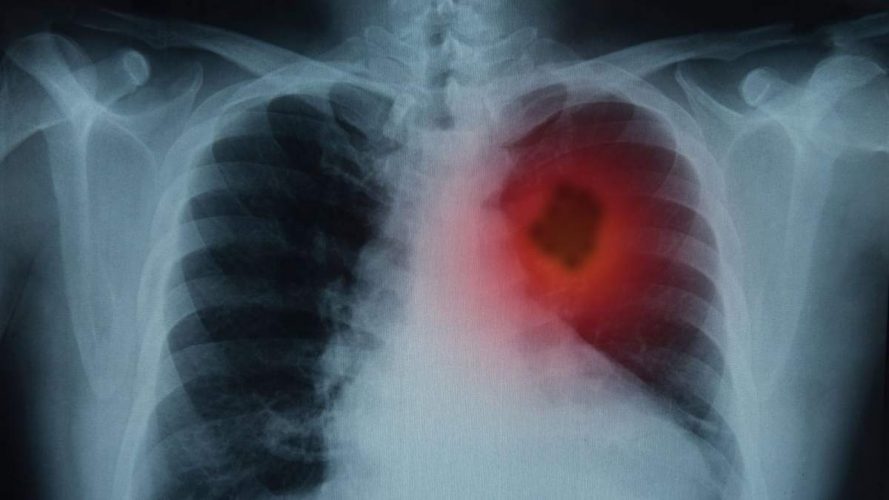

Рак легень – це один із найтяжчих та найпоширеніших видів онкологічних захворювань. Він займає особливе місце серед причин смертності внаслідок ракових захворювань у всьому світі. Щорічно в Україні реєструється понад 13 тисяч нових випадків раку легень, з яких значна частина виявляється на пізніх стадіях, коли лікування вже не може стати ефективним. Основні причини раку легень включають куріння, забруднене повітря та вплив канцерогенів. Це призводить до численних запитань про шляхи, методи та заключні етапи розвитку захворювання.

Розвиток раку легень зазвичай відбувається через кілька послідовних етапів. На початку захворювання клітини легень підлягають мутаціям через вплив навколишніх факторів, таких як куріння тютюну. З часом мутації накопичуються, що призводить до формування злоякісної пухлини. На ранніх стадіях рак може не виявлятися жодними симптомами, що ускладнює діагностику. Після цього хвороба починає прогресувати, викликаючи біль, задишку та інші фізичні розлади.

На різних стадіях раку легень можуть з’явитися різноманітні симптоми. У пацієнтів часто спостерігаються тривалі кашель, біль у грудній клітці та респіраторні інфекції. Виникають також системні симптоми, зокрема, втрата апетиту, надмірна втома та паління в грудях. Залежно від стадії розвитку, коли рак стає більш поширеним, з’являються метастази, які впливають на інші органи, ускладнюючи загальний стан пацієнта.

Особливі метастатичні ураження можуть включати поширення в печінку, кістки або головний мозок. Коли пухлина досягає 4 стадії, медикам часто доводиться боротися не лише з основним захворюванням, але й з його ускладненнями, такими як гостра дихальна недостатність, інфекції та зниження загального стану здоров’я. Кожен етап розвитку раку легень потребує індивідуального підходу до лікування і паліативної допомоги.